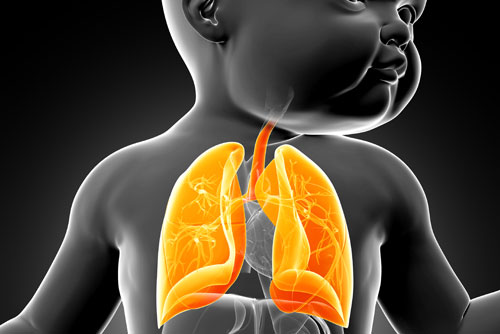

2- Akciğerde Oluşabilecek Hastalıklar

Anne karnında henüz dünyaya gelmemiş bebeklerde gelişebilecek hastalıklar da önceden tespit edilebiliyor. Bazen bebekte, akciğerin pek çok doğumsal hastalıkları söz konusu olabiliyor. Bu hastalıklar; akciğerin tam oluşmaması, akciğerde kistler, soluk ve yemek borusu arasında bağlantı olması gibi tanımlanıyor. Bebekte oluşabilecek bu hastalıklar annede herhangi bir bulgu oluşturmuyor. Sadece dikkatli bir ultrasonografik inceleme sonrasında tanı konulabiliyor. Tedavisi ise bebeğin ve hastalığın duruma göre doğumdan sonra yapılabiliyor.